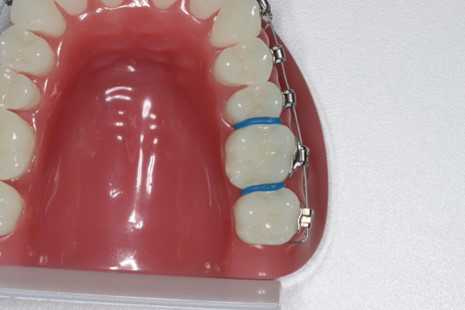

Placeres mellem 6-års tænderne hvis der skal sættes et bånd rundt om 6-års tænderne.

Det vil være nødvendigt at isætte separationselastikker ved 6-års tænderne.